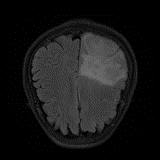

We obtain a subject-wise mean Dice score of 63.67% for the brain tumor segmentation. Utilizing a simple post-processing scheme of erosion and dilation with filter, we improve our mean Dice score to 68.01%. Figure 4 shows samples generated by our ASC-Net and Table 2 shows our before and after post-processing results. We attempted to apply f-AnoGANs [34] by following their online instructions and failed to generate good reconstructions as shown in Figure 5. The failure of AnoGANs in the reconstruction brings to light the issue with the regeneration based methods and the complexity and stability of GAN-based image reconstruction.

A most recent work in [27] trains their algorithm using 1,112 healthy scans from the Human Connectome Project (HCP) young adult dataset [38] and tests on 50 random BraTS 2018 scans, obtaining a mean dice score of 67.2% and 15.5% standard deviation. Following our simple post-processing scheme, our algorithm performs better, increasing the mean Dice score by 0.81% and reducing the standard deviation by 0.97%, on two-fold cross validation across 335 scans. Another work in [42] tests on the BraTS 2018 training set, obtaining a mean dice score of 71.63% and standard deviation of 0.84%. While their method outperforms ours, it is worth to mention that the self-supervised method is highly specialized to a particular task of tumor segmentation. It may happen that the object to be segmented is difficult to synthesize artificially or perfectly, resulting in a bottleneck of the pipeline. Furthermore, one assumption of a self-supervised learning algorithm is that the object to be learnt is known beforehand. Thus, a model trained for brain tumors cannot be applied readily to other anomalies, e.g., brain lesions. Our method, on the other hand, has no such limitations and does not need Pseudo dataset generation for a new task. That is, our method is a general approach for anomaly detection and segmentation. Also, our method performs better than [42] on the liver lesion segmentation task after post-processing.